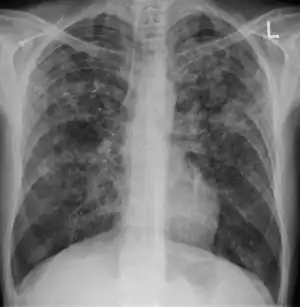

X-ray, showing extensive bilateral reticulo-nodular infiltrates